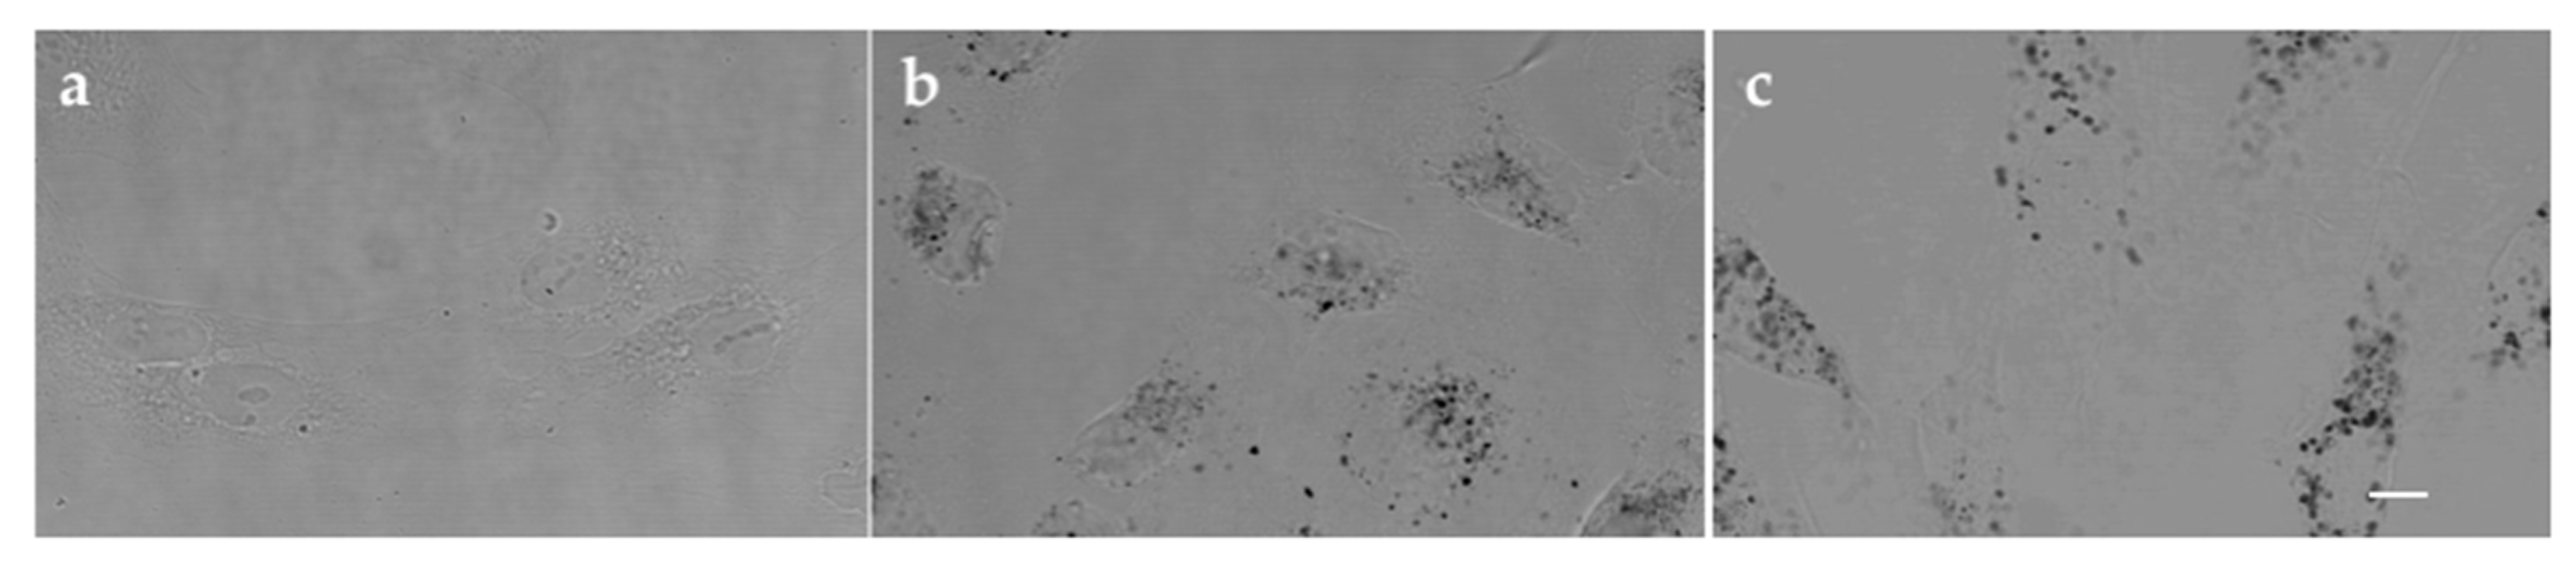

1. Introduction

2.8. Transmission Electron Microscopy (TEM) Analysis